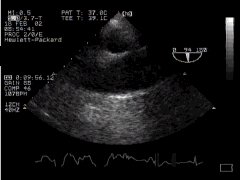

We can now rotate the probe to 90o to obtain another view of the arch, thus - 'Aortic Arch SAX':

Arch aorta - transverse section CLICK FOR VIDEO: Arch aorta SAX view